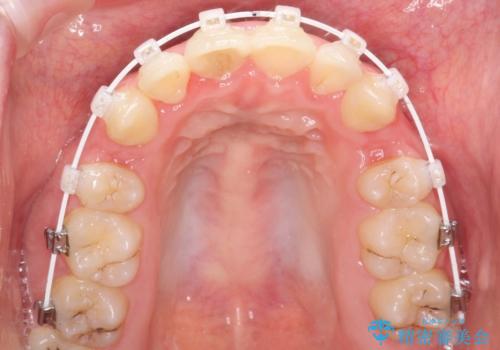

全体的ながたつき ワイヤーによる抜歯矯正で整った歯並びへ

- 審美

- 1年10ヶ月

- 上下の全体的ながたつきが気になるとのことで来院されました。

上下左右の前から4番目の歯を抜歯をして、ワイヤー矯正にて並べる計画としました。

患者様が装置を早期に除去したいという希望もあり、少々下の前歯のがたつきが残った状態で矯正を終了しました。

全体的ながたつきがなくなり、見た目の印象がよくなりました。